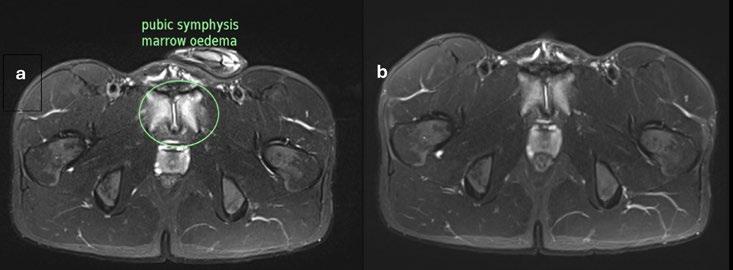

In order to assist in clinical decision making, MRI imaging was completed (Figure 1) which demonstrated severe diffuse pubic overload extending bilaterally into the superior and inferior pubic rami

Figure 1: Repeat MRI Imaging demonstrating pubic symphysis oedema at a) Baseline b) 31 days post-infusion c) 47 days post-infusion d) 59 days post-infusion

Due to the benefit of being able to perform repeat MRI imaging within an elite footballing setting this player underwent three post-intervention scans in order to provide longitudinal tracking of the bone and associated soft tissue oedema within the pubis which was proposed as the main driver of symptoms within this case (Figure One). Imaging was completed utilising the same 1.5T MRI scanner to ensure consistency in imaging to allow for genuine comparison.

Figure 1 demonstrates that there was improvement within the intensity of the bone marrow oedema within the first month following infusion. There was still some very small amount of residual associated soft tissue inflammation. This soft tissue inflammation resolved by seven weeks after the infusion and remained absent on imaging at nine weeks.

What can be seen from these repeat imaging points is that residual bone oedema and soft tissue inflammation did not correlate specifically with symptoms experiences by the player in this case. They remained pain free from two days postinfusion, but some levels of soft tissue inflammation were still present at onemonth post-infusion.